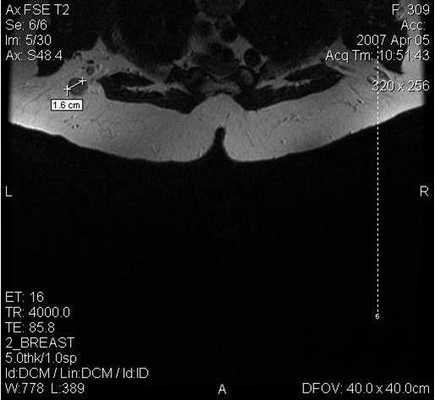

Поскольку традиционный маммографический скрининг у женщин до 40 лет малоэффективен, для скрининга может понадобиться альтернативная методика — МРТ. Современная контрастная магнитно-резонансная томография — высокочувствительный метод диагностики заболеваний молочной железы.

У женщин с мутациями BRCA1 или BRCA2 при проведении МРТ возможно диагностировать рак молочной железы на самых ранних стадиях.